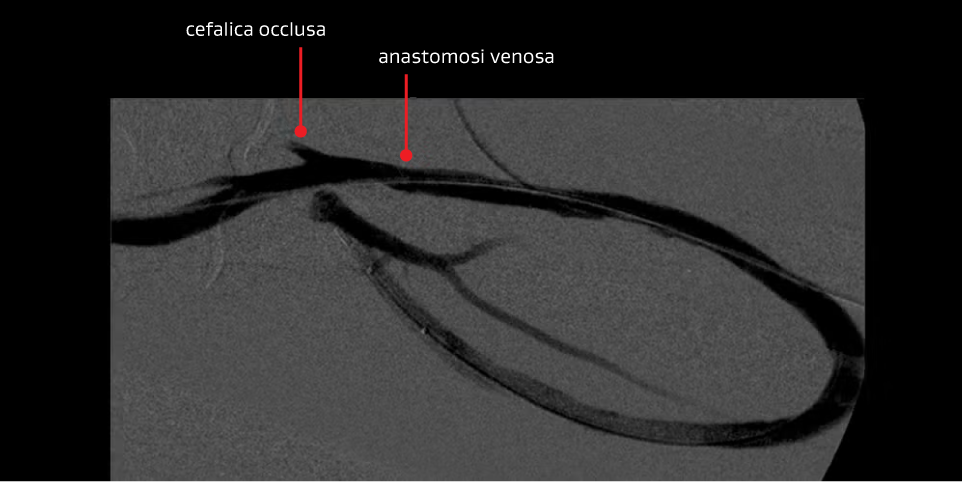

Secondo intervento — È stata scelta nuovamente la PTA di declotting per trattare la protesi trombizzata.

Intervento PTA di declotting:

- Solo 12 giorni dopo il primo intervento.

- Il paziente si è presentato di nuovo con la protesi trombizzata secondaria alla severa stenosi anastomotica venosa.

Motivazione per il trattamento:

- Continuare a dare alla lesione un'opportunità di “dichiarare la sua storia naturale”

- KDOQI 6.6 – Se è necessario ripetere l'angioplastica della stessa lesione per più di due volte in un periodo di tre mesi, si deve considerare di sottoporre il paziente a revisione chirurgica se è tuttora un candidato idoneo per l'intervento chirurgico

- Non ha ancora superato la raccomandazione della KDOQI

Risultato:

- Ancora una volta un buon risultato angiografico iniziale con flusso ripristinato; tuttavia, il paziente si è ripresentato dopo 28 giorni con una protesi trombizzata

Immagini per gentile concessione dei Minneapolis Vascular Physicians. Utilizzate con autorizzazione.